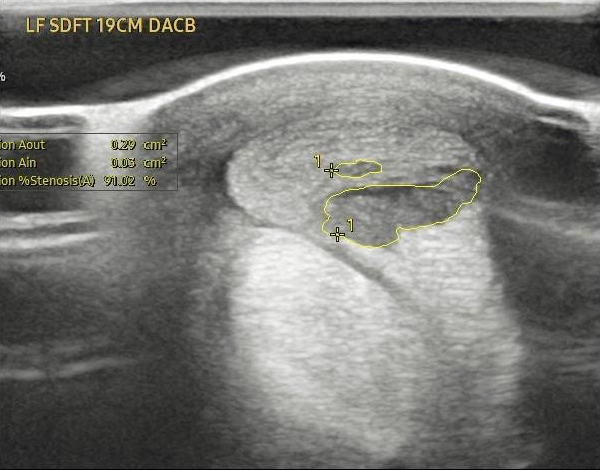

Case Study 1 – Equine Tendon Regeneration

The attached images display a pre- and post-treatment of an equine superficial digital flexor tendon injury, which is roughly the same size as a human Achilles tendon.

A single dose of Tropoflex joint formulation led to a decrease in the core tendon lesion from 91% stenosis to 1.5% stenosis over three months.

Source: Temecula Creek Equine